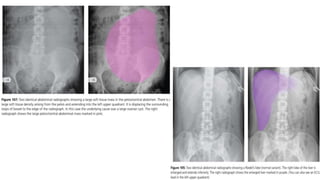

PORTAL VENOUS GAS

Branching dark lines within the periphery of the liver.

High mortality rate.

Main causes:

1. ischaemic bowel (most common)

2. necrotising enterocolitis (NEC) – most common in infants.

3. severe intra-abdominal sepsis

PNEUMOBILIA

Branching dark lines within the centre of

the liver , more prominent towards the

hilum.

Main causes :

1. Recent ERCP/ incompetent sphincter

of Oddi (post sphincterotomy)

2. External biliary drain insertion/

biliary stent insertion

3. Biliary-enteric connection

Surgical anastomoses (eg whipple’s

procedure)

Spontaneous (eg Gallstone ileus)

4. Infection(rare) – emphysematous